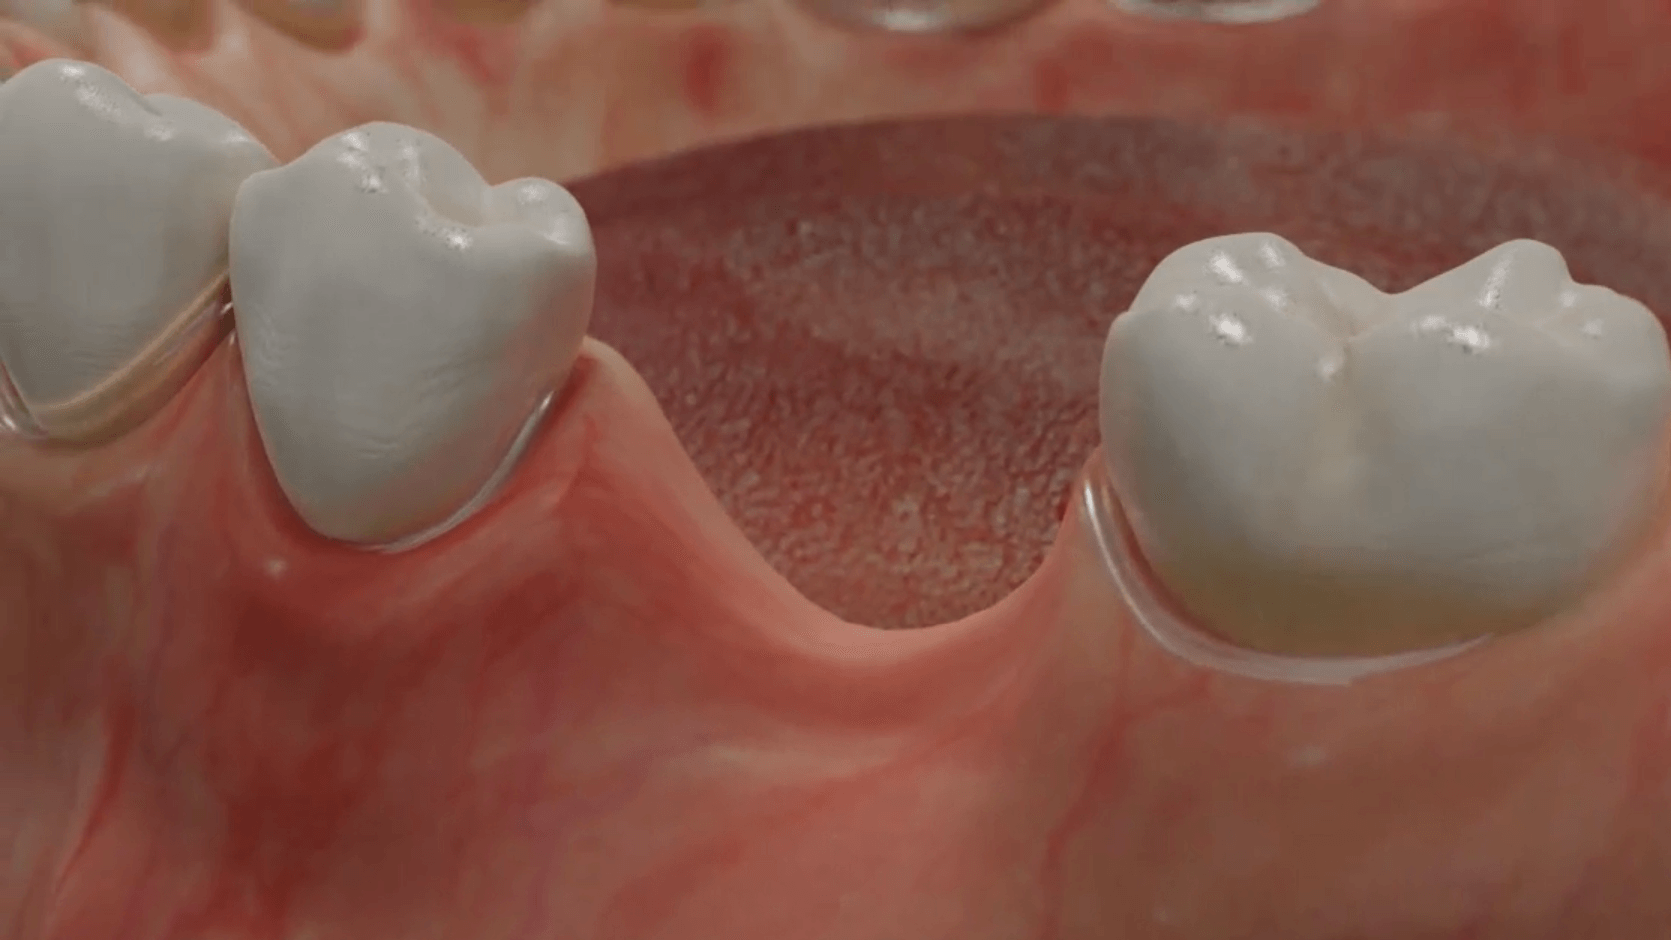

Durch den Verlust des Zahnes wandelt sich der Kieferknochen um. Nach der oberflächlichen Heilung wird das knöcherne Zahnfach vom Körper rasch abgebaut. Knochen ist für den Körper ein "teures" Gewebe, und ohne die funktionelle Kaubelastung durch einen Zahn gibt es für den Körper keinen Grund mehr, das knöcherne Zahnfach zu erhalten. Allein im ersten Jahr nach der Zahnentfernung gehen 50% des umgebenden Knochens verloren! Das ist insbesondere dann von Nachteil, wenn geplant ist, später ein Implantat für den Ersatz des Zahnes zu setzen. Ohne kiefererhaltende Maßnahmen reicht oftmals der nach der Heilung verbliebene Knochen nicht mehr aus, ein hinreichend großes Implantat einzusetzen bzw. dieses auch ideal zu positionieren.

Aus diesem Grund werden seit vielen Jahren

Knochenersatzmaterialien aus tierischem, pflanzlichen oder mineralischen Ursprung verwendet, um die Schrumpfung des Kieferknochens aufzuhalten und dadurch die ursprünglichen Dimensionen zu bewahren.